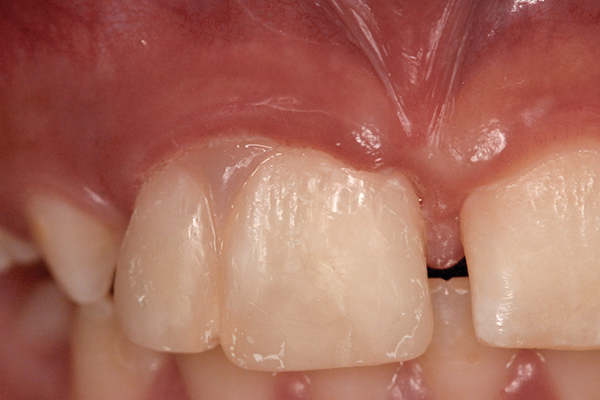

Fig 1 and Fig 2. Pretreatment photographs. Patient at 9 years of age on presentation.

A 9-year-old girl, referred to a prosthodontic office by her pediatric dentist, presented with her mother’s chief complaint: “The kids are teasing her about her big front tooth.” Findings from radiographic and clinical examinations revealed fused maxillary central-peg lateral incisors, teeth Nos. 7 and 8, and a congenitally missing lateral incisor, tooth No. 10 (Figure 1 through Figure 3). An implant was selected as the ideal treatment to replace tooth No. 10 when somatic growth was complete. A diagnostic wax-up was fabricated to determine if the fused tooth could be made to resemble two teeth, using pink composite to give the illusion of an interproximal papilla. The patient was referred for an orthodontic consultation to plan for closure of the diastema between teeth Nos. 8 and 9 and achievement of proper alignment for implant No. 10. The patient was also referred to a periodontist for pretreatment assessment of the tooth No. 10 site. An endodontist was consulted should exposure of the large pulp occur during tooth preparation.